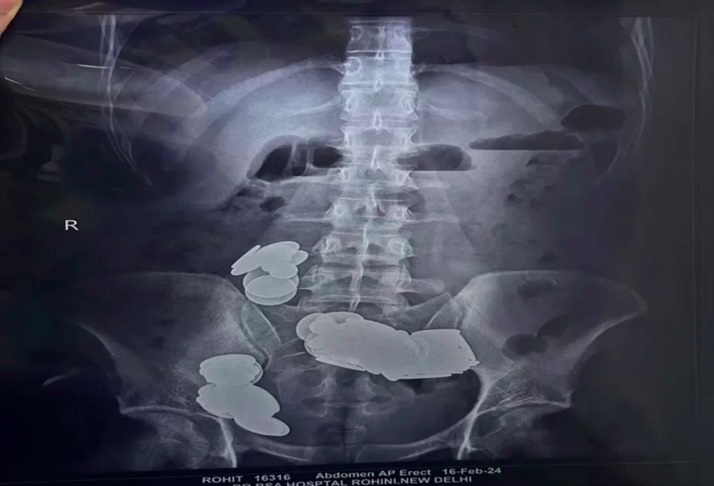

Pra quem não viu: Homem engole 39 moedas e 37 imãs para ‘ajudar na musculação’